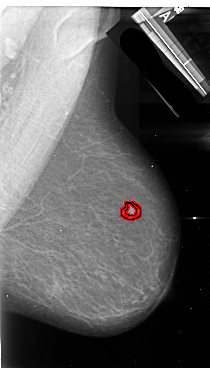

A_1093_1.LEFT_CC

RIGHT_CC LINES 4951 PIXELS_PER_LINE 3226 BITS_PER_PIXEL 16 RESOLUTION 42 OVERLAY

FILE: A_1093_1.RIGHT_CC.OVERLAY

TOTAL_ABNORMALITIES 1

ABNORMALITY 1

LESION_TYPE MASS SHAPE IRREGULAR MARGINS SPICULATED

ASSESSMENT 5

SUBTLETY 4

PATHOLOGY MALIGNANT

TOTAL_OUTLINES 1

BOUNDARY